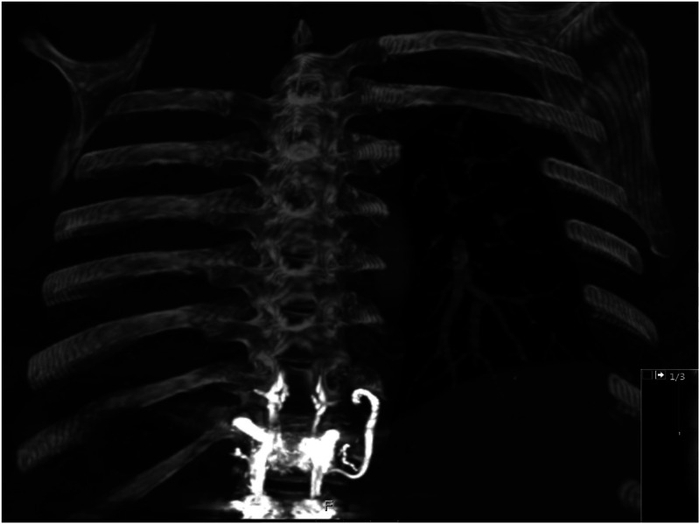

经皮椎体成形术是治疗骨质疏松引起的椎体压缩性骨折的重要手段,椎体成形术和椎体后凸成形术是最常用的方法。此类手术需将聚甲基丙烯酸甲酯(PMMA)或骨水泥被注入目标椎体以减轻疼痛并稳定椎体。此类手术73%的并发症与骨水泥渗漏相关,其中,骨水泥肺栓塞是相对少见但可危及生命的并发症之一,其发生率为2.1%~26%[4]。这种并发症可能导致机械性阻塞,出现如呼吸困难和疼痛的症状,通常在手术后数周至数月内显现。

第一位患者,在术后出现相关呼吸系统症状,由于观察到高密度以及表明肺动脉高压的右/左心室比值增加,可能是由在Th11-L3进行的椎体成形术引起的,因此怀疑骨水泥肺栓塞。

第二位患者,侧位片明显发现不透明影走向,在排除其他可能胸痛病因后,最终确诊为肺水泥肺栓塞。肺水泥肺栓塞是经皮椎体成形术的已知并发症,因聚甲基丙烯酸甲酯泄漏至系统静脉而发生。此过程通常始于前外静脉丛,进而进入奇静脉、下腔静脉、右心房,最终到达肺血管床,与本患者影像表现高度一致。